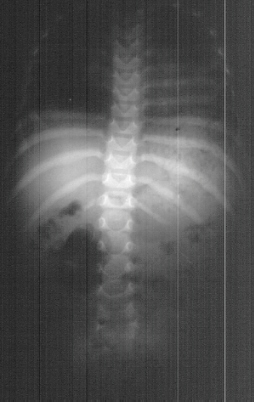

Radiographic evaluation at age of 3 showed mild scoliosis

and bilateral dislocated hips.

- Spinal Deformity

- 100% of type II, and most of Type III develop scoliosis with resulting

decrease in pulmonary function

- Typically begins in the first decade of life, is progressive and resistant

to bracing